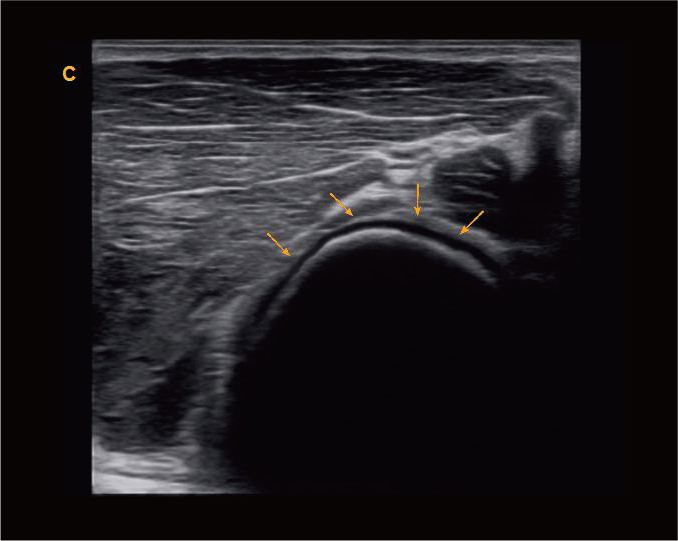

肘关节,B模式